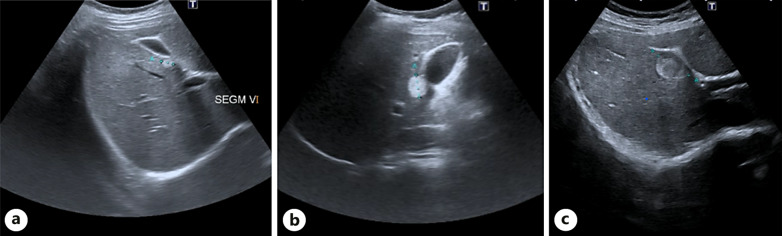

Case presentation: We present a case report of a 33-year-old female patient with a history of macroprolactinoma. She was initially referred to our Department due to a 9-mm hepatic nodule incidentally diagnosed in an abdominal ultrasound in 2018. She was asymptomatic. Follow-up ultrasound showed a growth from 9 mm to 16 mm in 2019 and 30 mm in a liver magnetic resonance imaging (MRI) scan in 2022. The case was discussed in a multidisciplinary team meeting, and since malignant transformation or hepatocellular carcinoma could not be ruled out, the decision was to undergo hepatic resection. An open hepatic subsegmentectomy of segment 5 was performed, with uneventful postoperative period. The definitive diagnosis was hepatic PEComa.